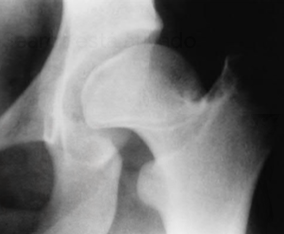

Principal alteração radiográfica

Achado radiográfico com obliquidade aumentada e perda da concavidade acetabular.

Sinais radiográficos tardios

Desenvolvimento de osteoartrite e subluxação do quadril.